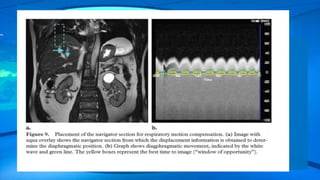

Real-time navigator echo gating is an elegant non–breath-hold technique that can be

used to compensate for several different types of motion .

Respiratory-ordered phase encodingworks well in patients with regular respiratory cycles but not in those with irregular breathing. Real-time navigator echo gating is an elegant non–breath-hold technique that can be used to compensate for several different types of motion .